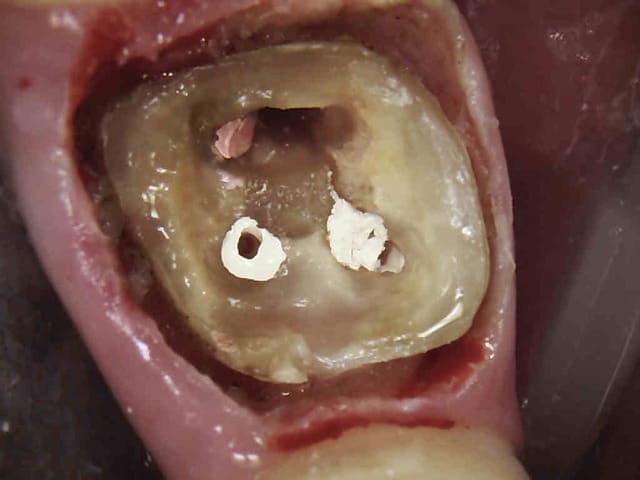

Ouh là , pansement enlevé c'est pas top !-))))

1 drovc7 - Eugenol

2 ylcwmn - Eugenol

3 el0lpw - Eugenol

Comment fait tu pour obtenir une éviction gingivale comme celle de tes photos

fraise fine, bistouri électrique, fraise fine, expasyl .

D'ailleurs si un adepte du laser pouvait témoigner de ses résultats ca serait bienvenu, ca chauffe moins en principe.-))))